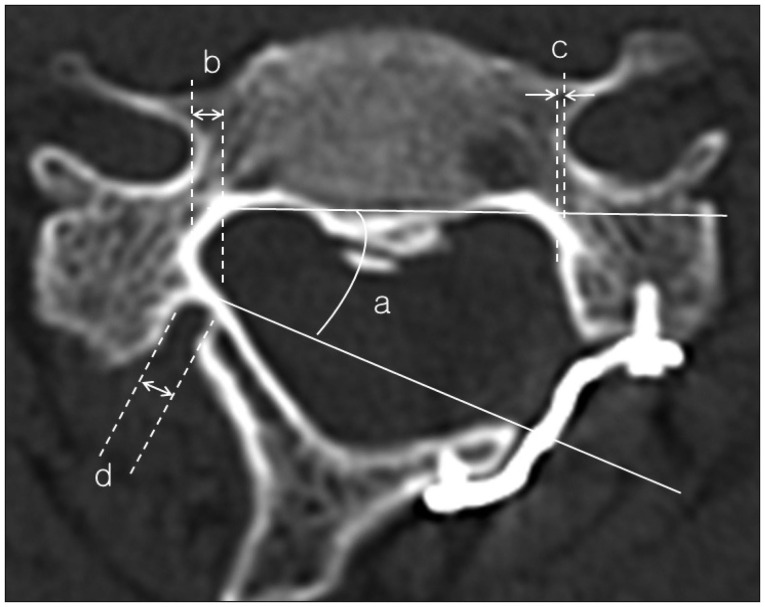

CT scanning was performed with a 16-multidetector CT (MDCT) scanner (Sensation; Siemens, Erlangen, Germany). Images were reconstructed using 2-mm-thick sections with no intervals and were optimized for evaluation of bony structures (width, 1500; center, 450). Postoperative axial CT scans were independently evaluated by three different reviewers (three neurosurgeons). The initial status of the hinge gutter and delayed HFs were evaluated as described previously (Table 2)10). Briefly, hinges were defined as deformed if the ventral cortices were bent but not broken (non-HF). The number of slices with a broken or disconnected inner cortex was counted among six or seven thin slices of CT scans obtained from a single lamina (Dx) which indicates poor hinge status as disconnected number increases. If all of the inner cortices were broken, it was defined as fractured, and if the inner cortices had moved inside, it was defined as migrated and these are all considered as HFs. In later observations, primary union (PU) was considered as non-HF. Contrastively, nonunion, callus formation, and secondary union (SU) which demonstrates healing process occurred after fracture were considered as HF. The healing status of each lamina was determined by consensus of two or more of the three reviewers. Fig. 1 shows radiographic measurements of hinge-side gutter and open-side gutter location, open angle, and hinge width.

Fig. 1. Radiographic measurements of a) hinge open angle, b) hinge gutter location, c) open gutter location, and d) hinge gutter width.